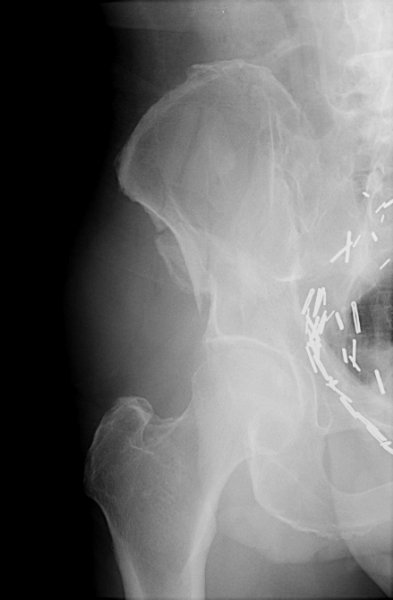

Return to Duverney Fracture